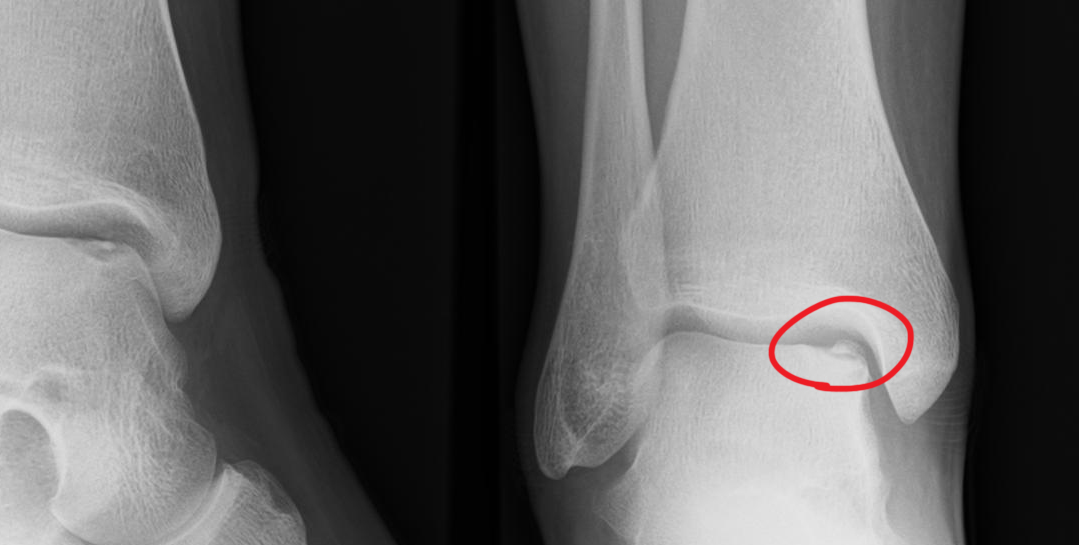

there's even talk of necessary surgery. I know it sounds serious and all, but it also sounds pretty ridiculous. So though it's quite restricting not being able to really walk, I have a hard time taking it too seriously at the moment.